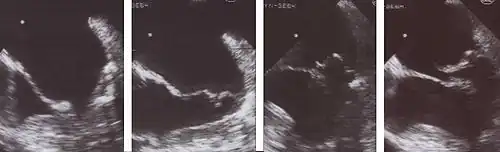

Echocardiogram

![]() |

Severe MR | Legend |

1 Left atrium (LA) – 2 MR Jet, LV Left ventricle – RV Right ventricle – RA Right atrium |

An echocardiogram is commonly used to confirm the diagnosis of MR.[16] Color doppler flow on the transthoracic echocardiogram (TTE) will reveal a jet of blood flowing from the left ventricle into the left atrium during ventricular systole. Also, it may detect a dilated left atrium and ventricle and decreased left ventricular function.[6] A transesophageal echocardiogram can give clearer images if needed as the back of the heart can also be viewed.[17]